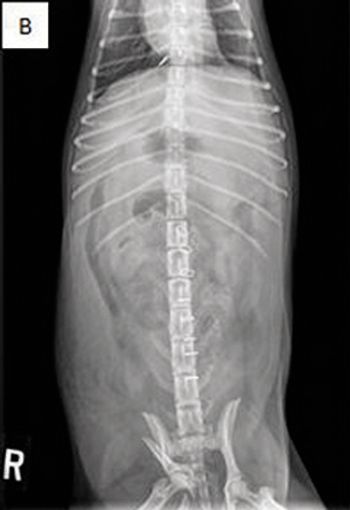

The causes of urinary incontinence classically are divided into neurogenic or non-neurogenic categories.